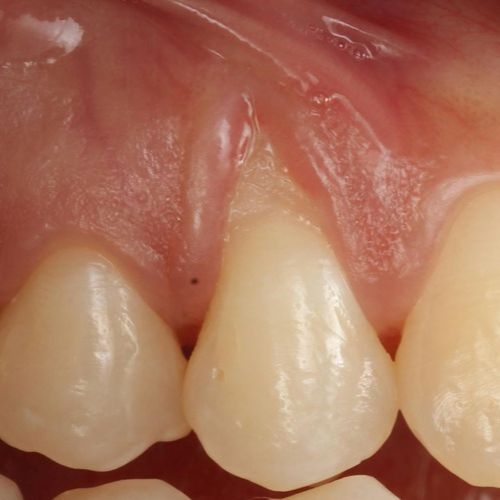

![]() | ![]() |

| Free gingival graft surgery’ to thicken gum and prevent further recession | Gum recession surgery in an aesthetic site |